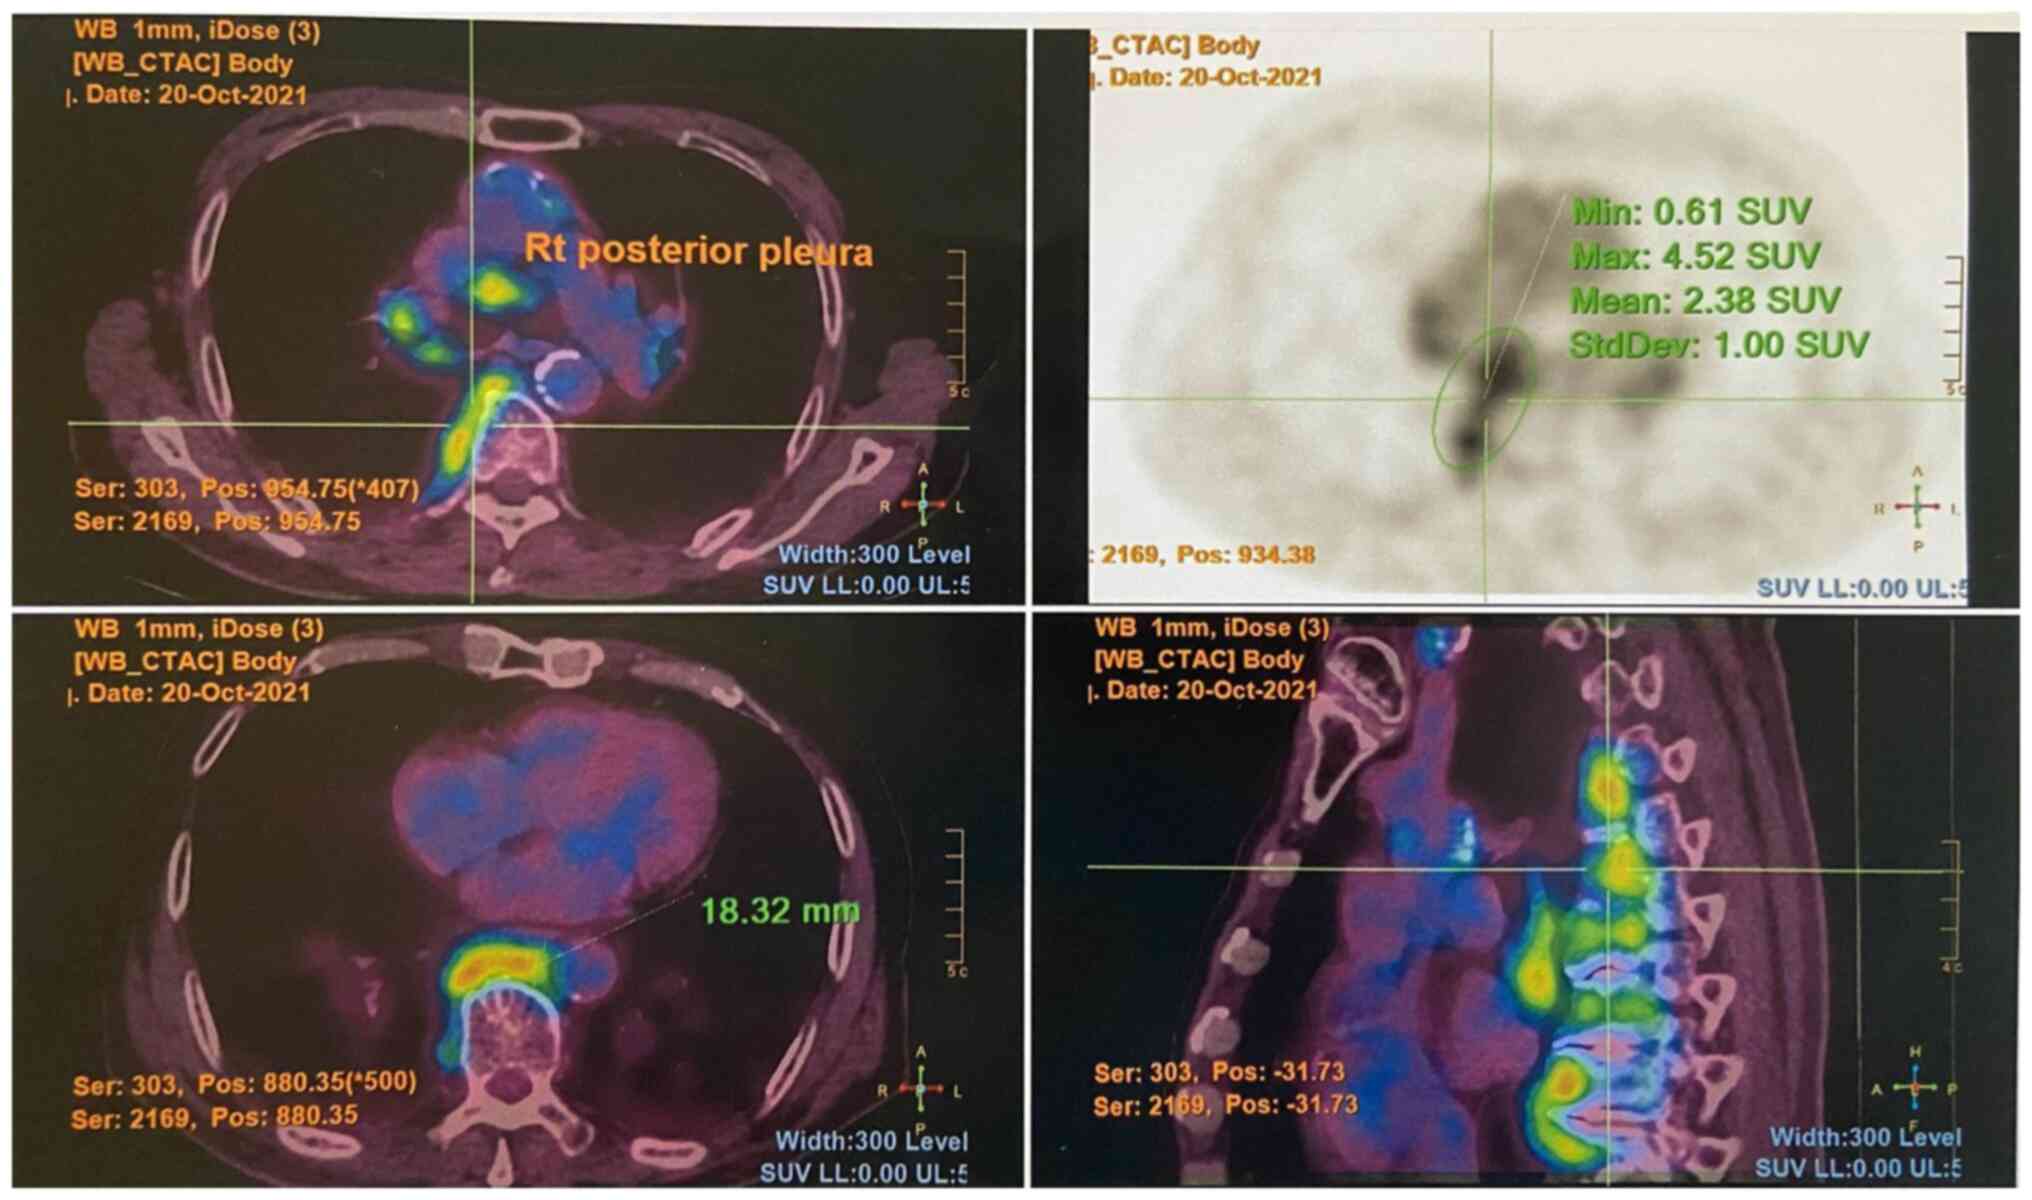

The levels of tumor markers, including alpha fetal protein (3 µg/l), prostate-specific antigen (<0.03 µg/l) and carcinoembryonic antigen (1.9 µg/l) were withiun normal range. He had an increased eosinophil count (1.9x109/l; reference range, 0.0-0.5x109/l) and an erythrocyte sedimentation rate of 119 mm/h (reference range, <32 mm/h). Autoimmune markers including antinuclear, antineutrophil cytoplasmic, Sjögren syndrome-related antigen A/Ro, Sjögren syndrome-related antigen B/La, double-stranded DNA, ribonucleoprotein and Smith antibodies were all negative. His serum IgG4 count was increased (2,269 mg/dl; reference range, 9-146 mg/dl). A positron emission tomography-computed tomography scan revealed multiple fludeoxyglucose F18 (FDG)-avid enlarged mediastinal, hilar, (Fig. 1) and submandibular lymph nodes, as well as an FDG-avid right parotid gland nodule. An FDG-avid nodular thickening of the right posterior pleura was also noted at the T9/10 level (Fig. 2).

Figure 2

PET/CT image illustrating an FDG-avid nodular thickening of the right posterior pleura at the T9/10 level. The top left image is a transverse cut fusion (PET/CT) image at the mid-thoracic level. The top right image is a transverse cut PET image. The bottom left image is a transverse cut fusion (PET/CT) image at the lower thoracic level. The bottom right image is a sagittal cut fusion (PET/CT) image. PET/CT, positron emission tomography-computed tomography.